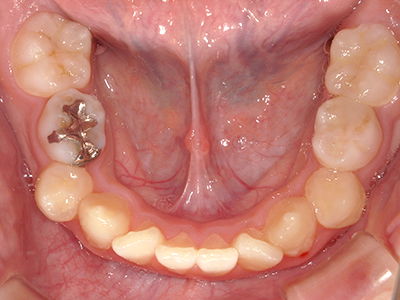

矯正装置を装着し、調整しながら少しずつ歯を移動させ、歯並びを整えていきます。